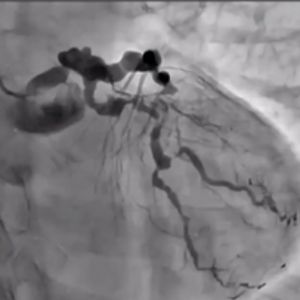

Join us for a live-streamed workshop where the world's top cardiologists gather to explore cutting-edge techniques in PCI (Percutaneous Coronary Intervention), with a special focus on the advanced Tip Detection Antegrade Dissection Re-entry (TD-ADR) method.

- Innovative Techniques: Master the latest technologies, including the highly-regarded 3D wiring technique and TD-ADR, developed in Japan, and stay at the forefront of medical innovation.